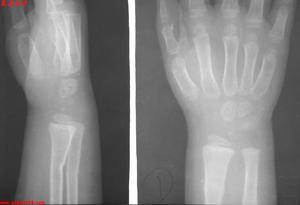

1、對無移位或移位不多而不影響鏇轉功能的橈骨小頭骨折,如嵌插性骨折,關節面傾斜度30度以下,塌陷性骨折占周徑1/3以內者採用手法整復,石膏托固定,三角巾懸吊。

2、橈骨小頭骨骺分離有移位者,在麻醉下整復。

3、切開復位:切開復位後,一般不用內固定,若不穩定,則用一根克氏針內固定。

4、橈骨頭切除術:只適用於成年人,如粉碎性骨折,塌陷性骨折超過周徑1/3者,嵌插性骨折關節面的傾斜度在30度以上者,一般在傷後4-5天,切除橈骨頭1-1.5厘米,將斷端修平,骨碎片清除乾淨,術後三角巾懸吊肘關節於功能位,二周即開始活東。

手法復位一、伸直型骨折治療以手法復位外固定治療為主,很少需要手術治療。

(一)手法復位外固定

1、麻醉局部麻醉。

2、體位仰臥。

3、牽引肩外展90度,助手一手握住拇指,另一手握住其餘手指,沿前臂縱軸,向遠端牽引,另一助手握住肘上房作反牽引。

4、復位充分前因後,術者雙手握住腕部,拇指壓住骨折遠端向遠側推擠,2—5指頂住骨折近噸加大屈腕角度,糾正成角,然後向尺側擠壓,緩慢放鬆牽引,在屈腕尺偏位檢查骨折對位對線情況及穩定情況。

5、用超腕關節小夾板固定或石膏夾板固定2周,水腫消退後,在腕關節中立位繼續用小夾板或改用前臂管型石膏固定。